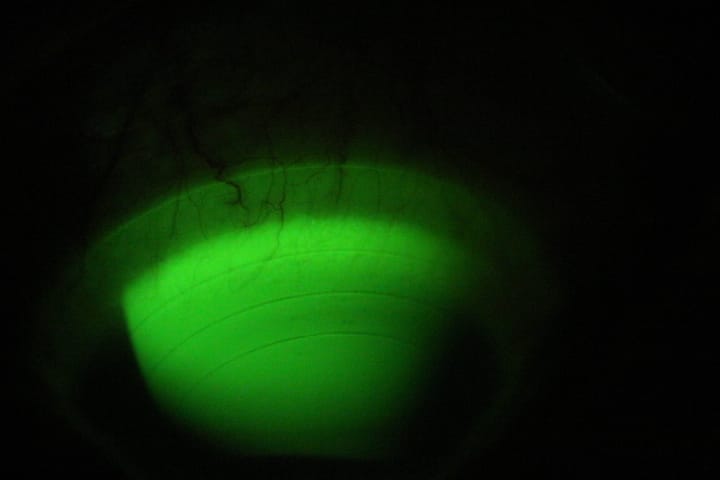

Huellas de lente escleral Ajustado (Neovascularización).